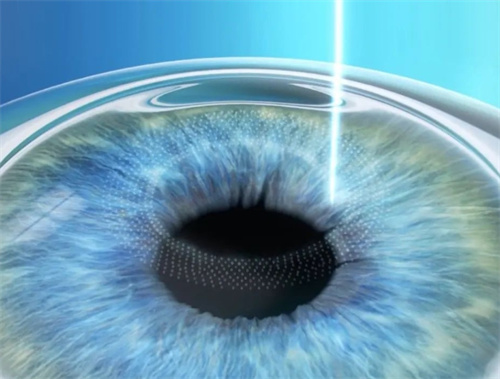

人工晶体置换需通过角膜切口将人工晶体植入眼内,若术中无菌操作不严或术后护理不当,细菌可能通过切口侵入眼内,引发眼内炎。

人工晶体依赖周边囊袋固定,若术中囊袋撕裂、术后剧烈运动或眼部受到外力撞击,晶体可能发生偏移或脱位。

手术可能影响房水循环,导致眼压升高。若眼压持续处于高位,会压迫视神经,引发青光眼。部分患者术后需长期使用降眼压药物,甚至接受激光治疗以控制病情。